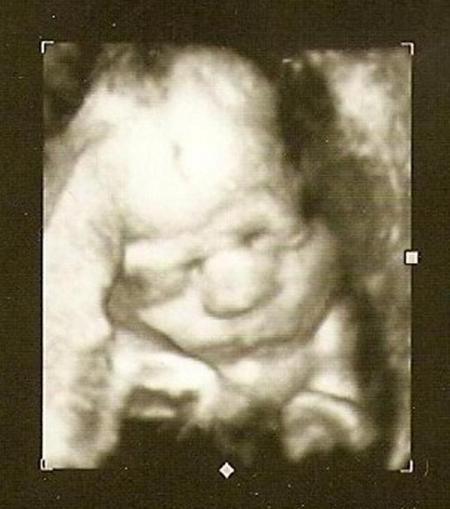

Hallo! Wie süß! Hier mal mein Zwerg in der 31. Woche. Gruß Kathrin